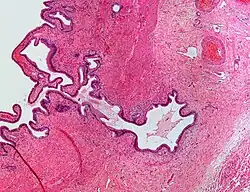

| Micrograph showing Rokitansky–Aschoff sinus. H&E stain. |

Rokitansky–Aschoff sinuses are pseudodiverticula or pockets in the wall of the gallbladder. They may be microscopic or macroscopic. Histologically, they are outpouchings of gallbladder mucosa into the gallbladder muscle layer and subserosal tissue as a result of hyperplasia and herniation of epithelial cells through the fibromuscular layer of the gallbladder wall.[4]